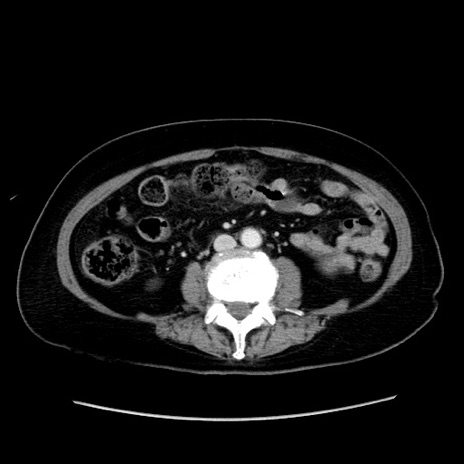

症例19(横断像)

【症例】80歳代女性

【主訴】下腹部痛

【現病歴】約8時間前より下腹部痛の出現あり、救急外来受診。

【既往歴】両側付属器切除

【身体所見】意識清明、下腹部正中に手術痕あり、その部位に一致して圧痛と反跳痛あり。腸蠕動音は亢進。

【データ】WBC 9300、CRP 0.15